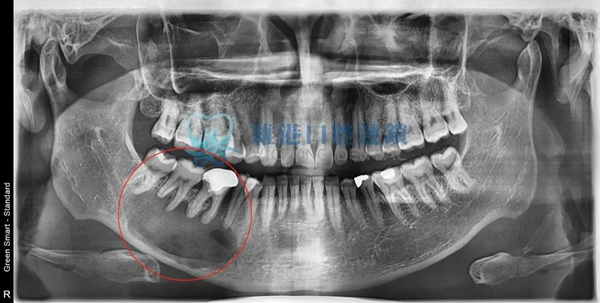

頜面囊腫波及根尖

輕微案例